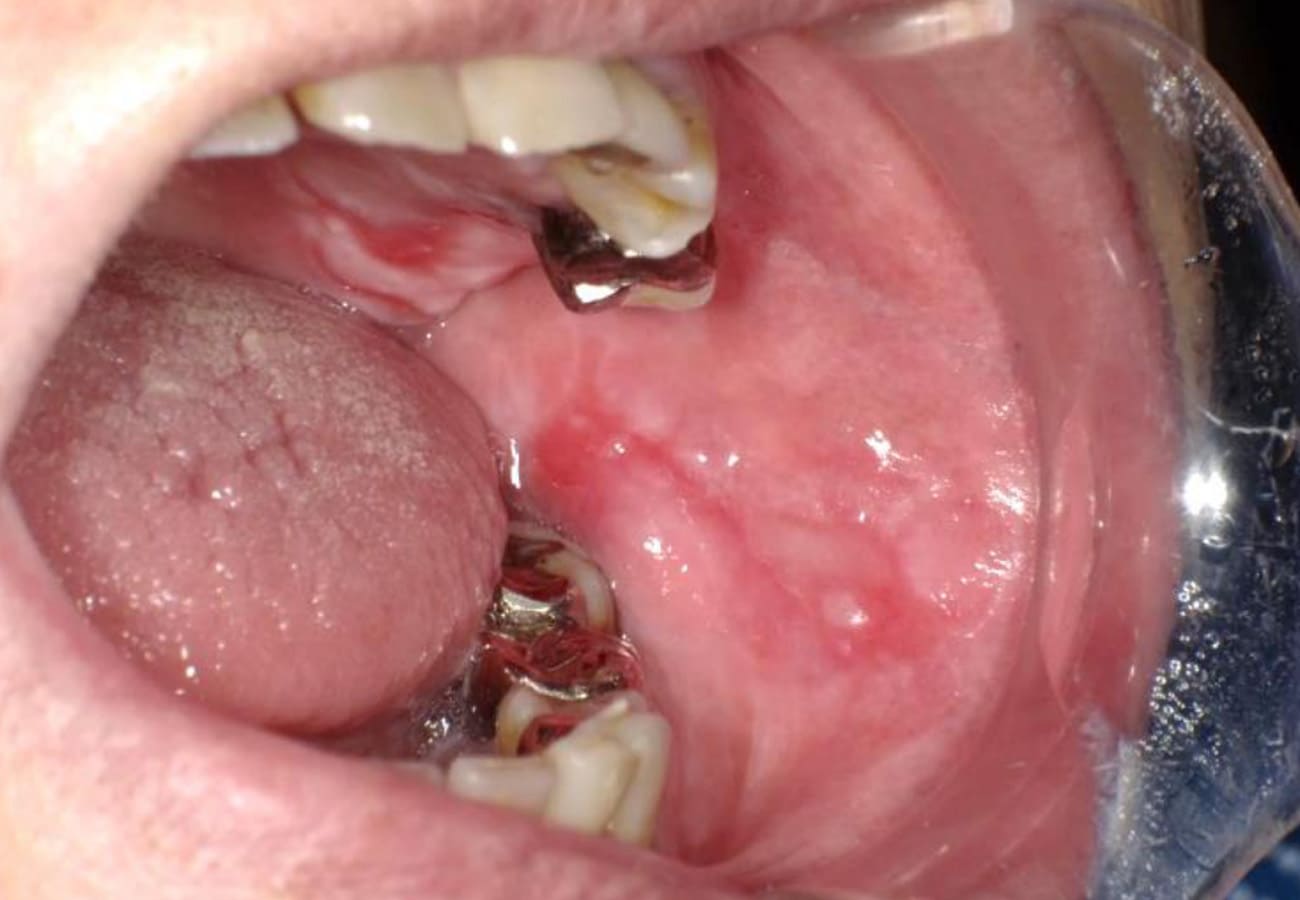

| 症状 | 粘膜に白いレース状の模様ができ、周囲が赤く腫れたり、ただれたりします。頬の粘膜に多く見られ、カレーなどの刺激物で強くしみるのが特徴です。 |

|---|---|

| 専門医の視点 | はっきりとした原因は不明ですが肝炎や金属アレルギー、ストレス、免疫異常が関与する場合もあります。口腔扁平苔癬は難治性(治りにくい)であることが多い疾患です。当院では原因の特定に努め、ステロイド軟膏による治療や、全身状態を考慮した管理を行います。 |